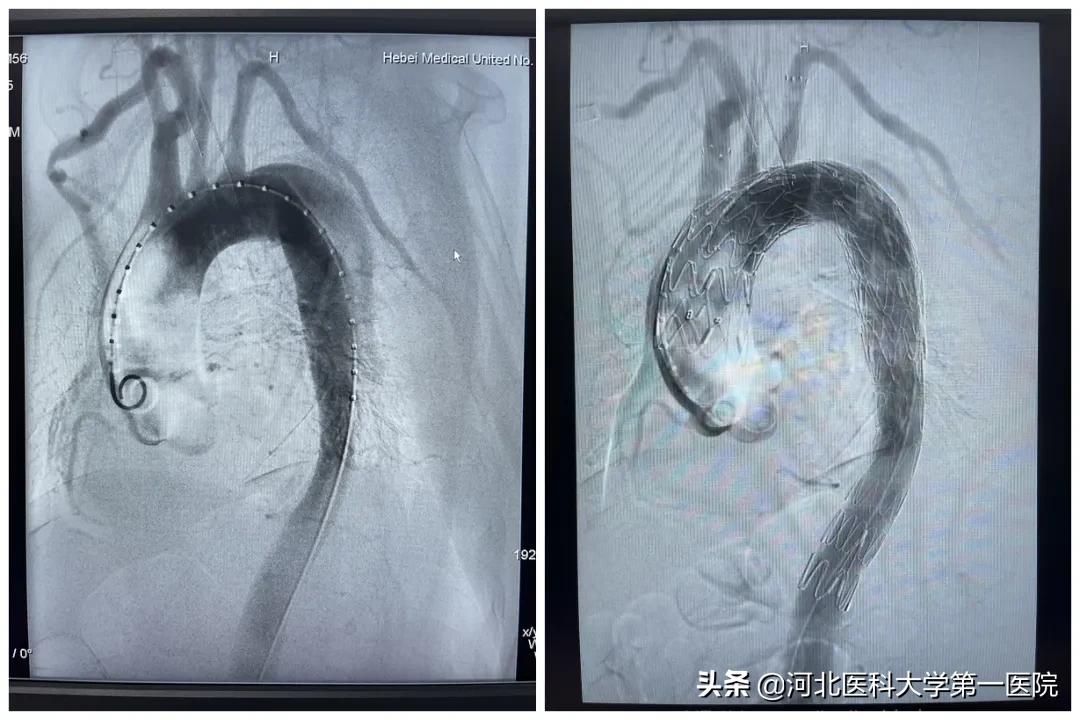

针对王大妈的检查结果,血管外科张磊主任带领团队立即联合麻醉手术室、重症医学一科进行治疗方案的讨论,大家决定为王大妈采用微创的“三开窗”技术,通过小切口在严重的夹层内,再造一个完全替代损伤的主动脉弓及分支的血管。

在血管里手术,并且还要在血管上做出来三个烟囱,这让家属听了不可思议。如此一来,手术无需开膛破肚,也不用流失大量的血液,在医生高超的技术支撑下,连体外循环都可以不采用。尽管风险很大,但家属们非常支持和配合。

为了保障器官供血,需要在最短的时间开三个窗口,并置入分支的血管,手术的难度和风险很大。夹层处的血管壁本身脆弱,放置支架不稳定,弯曲的弓部血管处还容易发生侧漏,即便是手术成功,还要防止“逆撕”发生。本就脆弱的血管,手术中就连血压稍有波动,也会导致决堤。

麻醉科在无体外循环的情况下,保障病人手术中全程的平稳,五个小时的手术,一个岌岌可危的主动脉夹层,在杂交手术室被顺利完成。王大妈被送入重症监护室进行后续的治疗,随后转入普通病房开始康复治疗。

作为独立完成的首例“三开窗”手术,张磊主任的团队支架置入恢复大脑血供,仅用了5分钟。也是我省最早开展的全腔内一次性全部重建头臂血管的微创手术,标志着我院血管外科在大血管疾病诊疗方面又迈上了一个新的台阶。